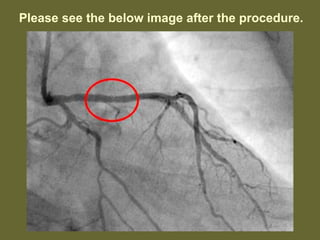

Please see the image below with red circle.

On 27th Octoberafternoon, I had severe heart attack symptom and I was rushed to the hospital. After reaching to the hospital, the doctors prescribed a test called angiogram. This test is basically to identify blood flow of heart arteries. When they finished the test they found a 94% block in the main artery.